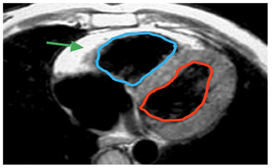

Αρρυθμιογόνος Δυσπλασία Δεξιάς Κοιλίας (συχνότητα 1:5000) Μυοκαρδιοπάθεια κατά την οποία ο μυοκαρδιακός ιστός της δεξιάς κοιλίας αντικαθίσταται σταδιακά από ινολιπώδη ιστό. Σε προχωρημένο στάδιο μπορεί να προσβληθεί και η αριστερά κοιλία. Έχει συνδεθεί με αιφνίδιο θάνατο νεαρών ατόμων και αθλητών. Διαπιστώνεται κληρονομικότητα σε >50% περιπτώσεων της νόσου.

Ταχυκαρδία ή καρδιακή ανεπάρκεια Οι ασθενείς υποφέρουν από αίσθημα παλμών στο στήθος, κρίσεις ζάλης, συγκοπτικό επεισόδιο. Το Ηλεκτροκαρδιογράφημα είναι χαρακτηριστικό (κύματα ε, ανεστραμμένα Τ v1-v3, ευρύ QRS). Στο Υπερηχοκαρδιογράφημα θα βρεθούν στη δεξιά κοιλία διάχυτη διάταση ή/και τοπικές υποκινησίες ή/και σακοειδείς διατάσεις. Η διάγνωση τίθεται με Μαγνητική Τομογραφία Καρδιάς